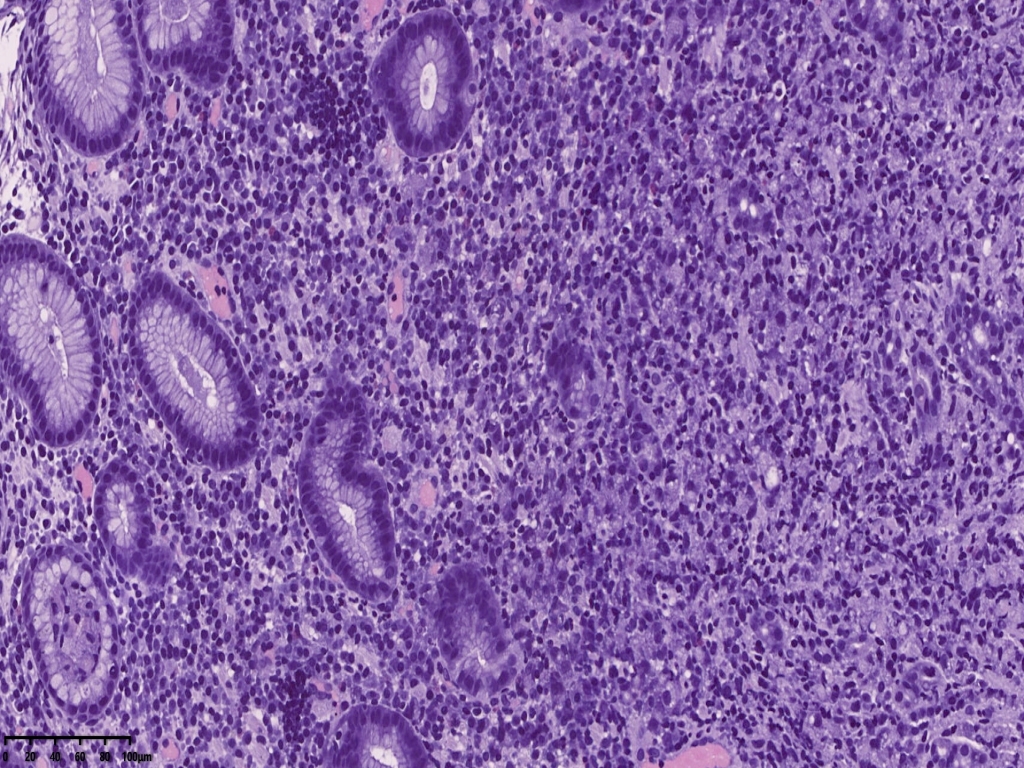

免疫组化常规片内异型上皮细胞更显著。核偏位的异型上皮细胞,胞浆似泡沫样,但是与组织细胞不同,组织细胞核位于中央,与印戒细胞也不太一样,印戒细胞胞浆内为明显的粘液空泡。

免疫组化标记后异型上皮细胞更显著。